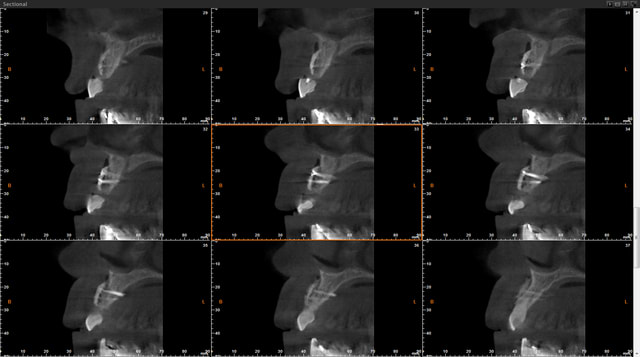

Je me permets de vous soumettre les clichés de scan à 5 mois d'une greffe d'apposition maxillaire antérieure secteur 11 12 que j'ai réalisée.

J'avoue avoir été surprise du hiatus qui existe encore entre greffon et os cortical initial, je suis d'ailleurs déçue je pensais que la forme que j'avais donnée permettait un meilleur "placage" du dit greffon.

D'après vous est ce que cette image est trop précoce dans le processus de cica et que mon "vide" va se combler dans les semainesà venir? je note bien l'intégration sur la crête et les bordures de la greffe.

ta 5 em coupe est pas si mal

sur la coupe 1 et 2 on percoit encore la corticale presqu'intact... on doit enclaver le bloc donneur dans l'os receveur

Il faut un contact intime du greffon avec le site receveur et ici cela ne devait pas être le cas sur toute la surface. Mais une partie semble bien minéralisée. Attends encore un mois avant d'intervenir, tu verras bien à ce moment là.

Je dois dire que quand j'ai reçu les images du scan j'ai fait défilé les coupes horizontales de cervical en apical et là j'étais ravie : on ne voyait cette maladaptation que dans une faible zone au tiers apical dans le creux de la concavité de 13. C'est après que j'ai déchanté.

Quand je fais circuler ma souris sur le logiciel de planification sur les zones "sombres" le logiciel m'indique une densité assez correcte très proche de celle de l'os spongieux du patient,du coup je me dis que la minéralisation est en cours....

Pourtant à partir de la coupe 142 on commence à voir une belle fusion entre les 2 surfaces.